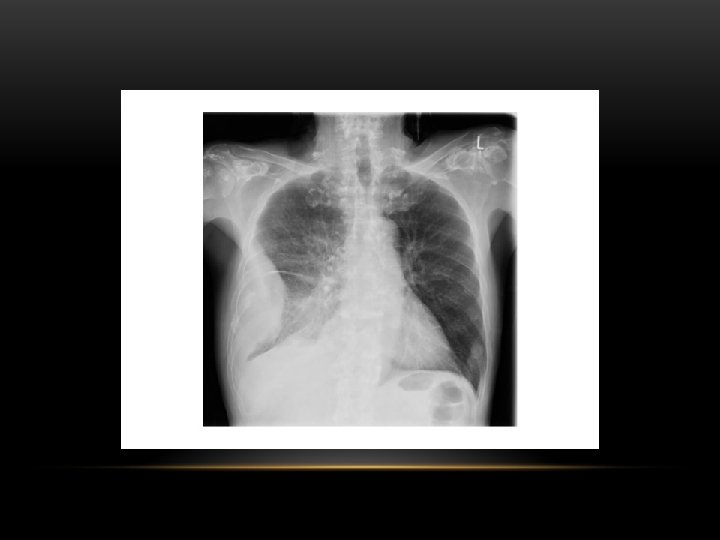

Pleural Fibrosis • Small right hemithorax • Diffuse haziness • Blunted costophrenic angle

Pleural Fibrosis Diffuse haziness Apical cap thickening Blunting of costophrenic angle Loss of lung volume